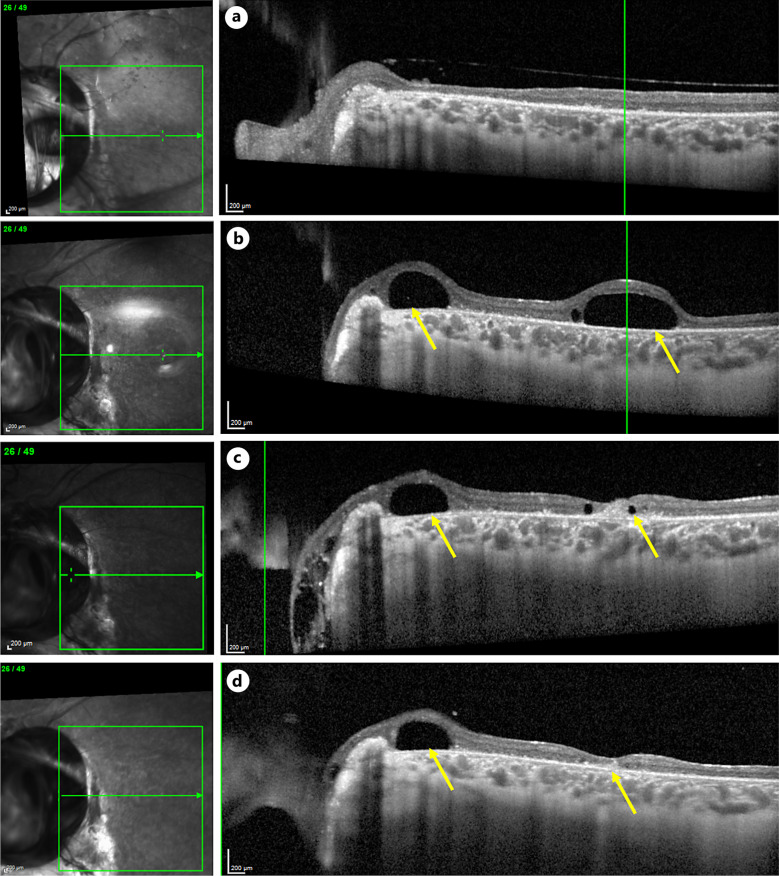

Case presentation: A 15-year-old male with a history of left eye congenital optic disc coloboma and amblyopia presented with a third recurrence of retinal detachment (RD) with proliferative vitreoretinopathy. The patient underwent PPV, subretinal fluid drainage through a peripheral retinotomy, silicone oil tamponade, and endolaser around the coloboma and retinotomy. The retina re-attached successfully. However, 14 months postoperatively examination revealed high intraocular pressure (IOP) of 33 mm Hg and a sub-macular bubble of silicone oil was evident. The patient underwent sub-macular silicone oil removal.

Conclusion: Here we describe the unique late-onset subretinal migration of intravitreal silicone oil following RD repair in an eye with optic disc coloboma in association with raised IOP. This case demonstrates potential mechanisms of subretinal silicone oil migration through the coloboma that serves as a passage and an increased IOP, which drives the oil from the vitreous to the subretinal space.